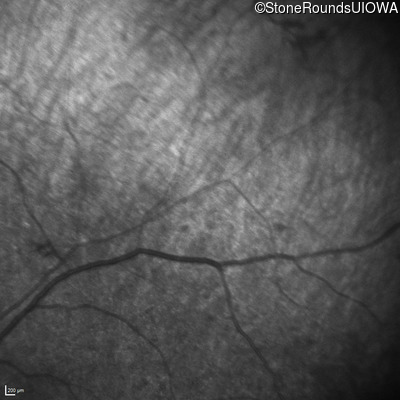

Infrared Fundus Photograph - Left - Light Perception

Exemplar